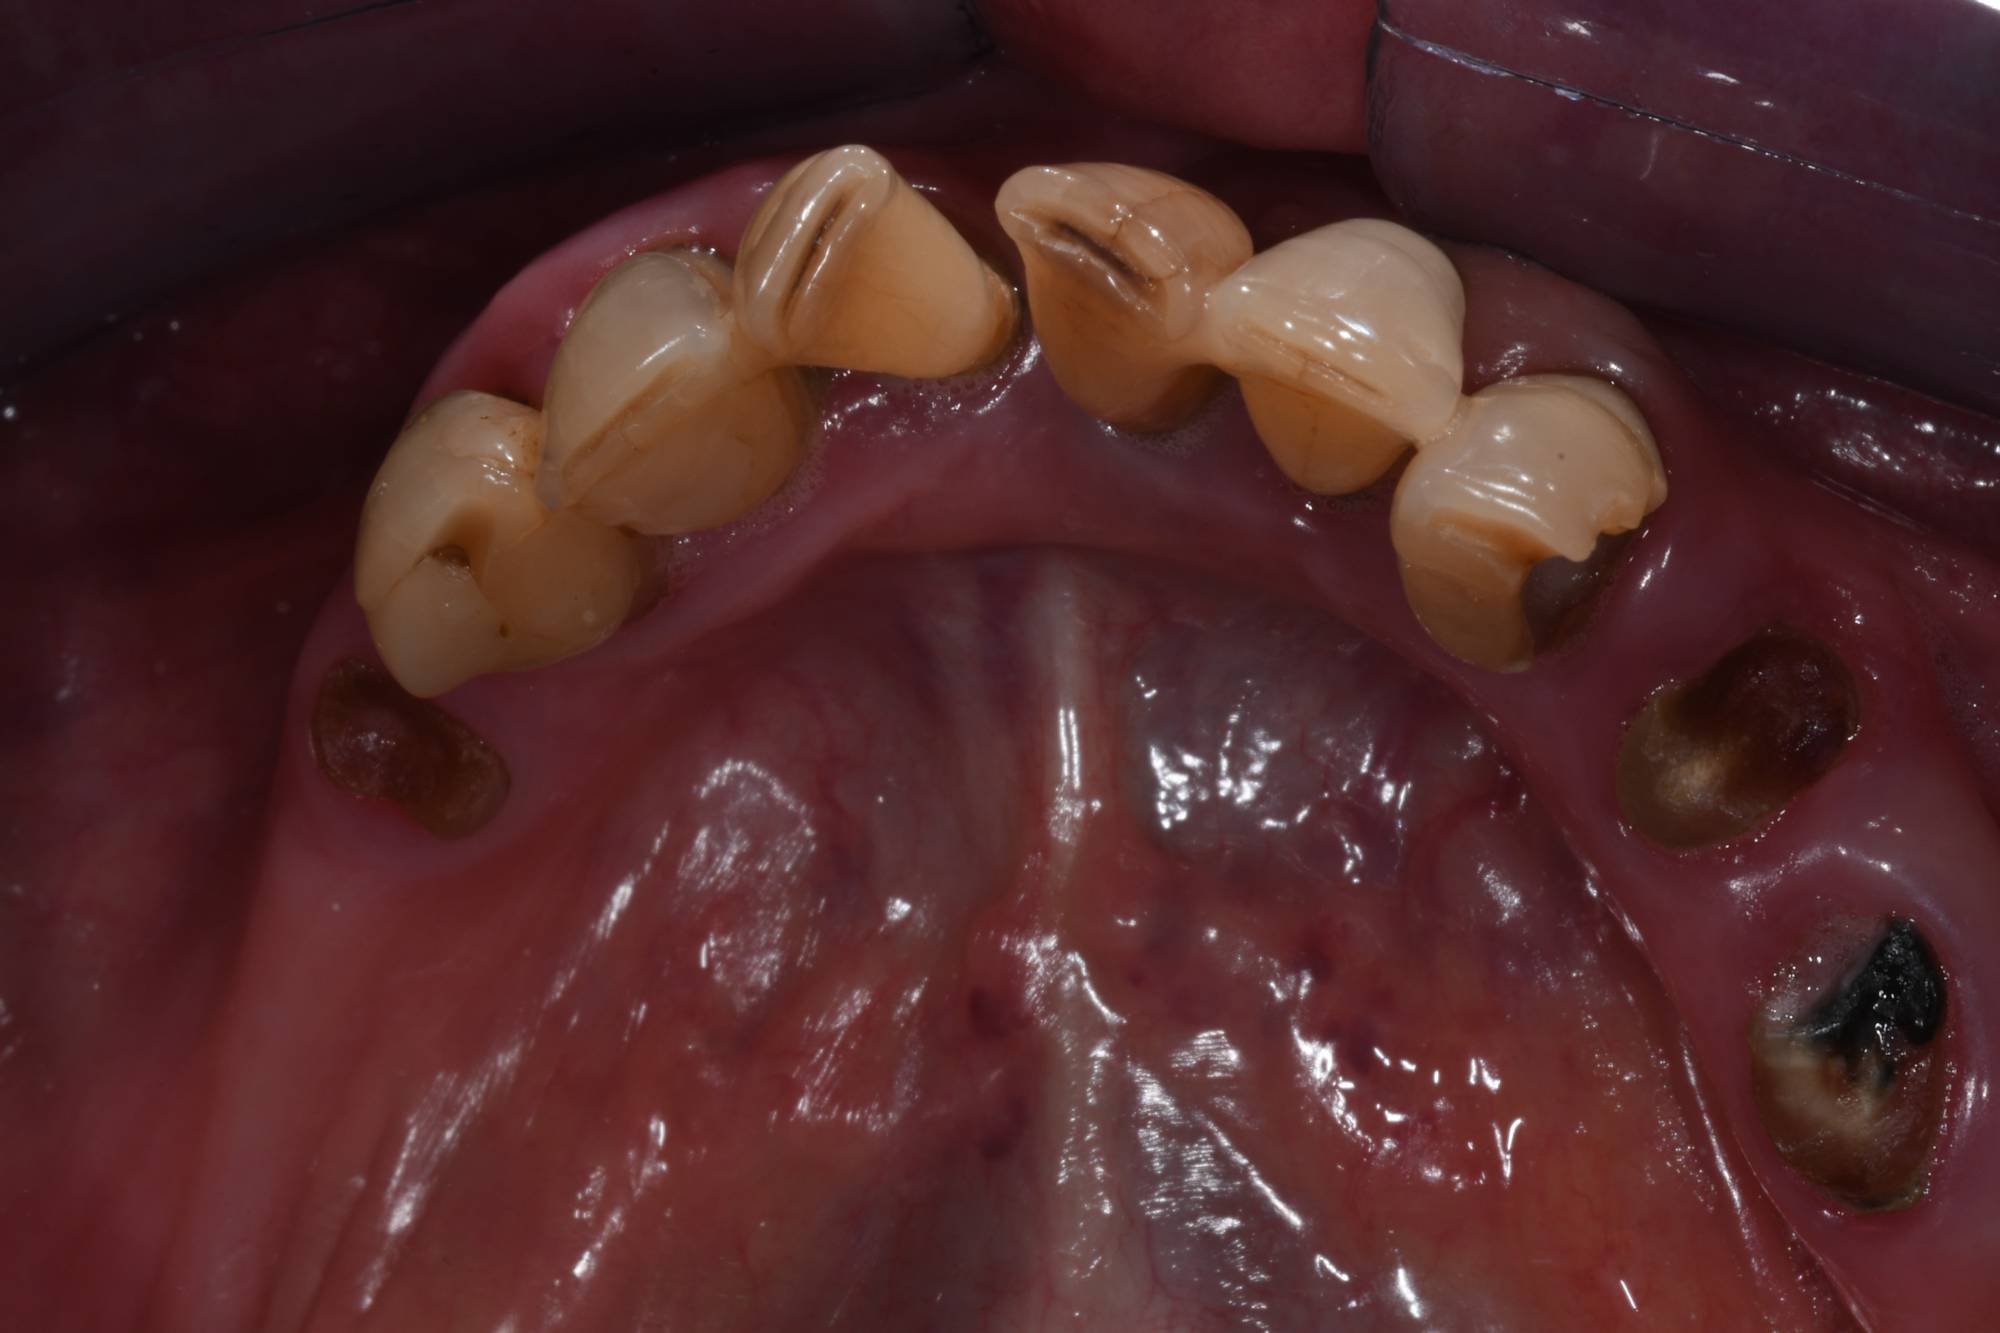

Come vedi dalle foto qui sotto, la paziente aveva perso numerosi denti e quelli rimanenti erano “traballanti”, pertanto non poteva più sorridere e mangiare normalmente. Per cui ho inserito gli impianti osteointegrati necessari per rimpiazzare tutta l’arcata inferiore. Nel giro di 2 giorni ha ritrovato sorriso e funzione con una protesi fissa provvisoria saldamente avvitata agli impianti.